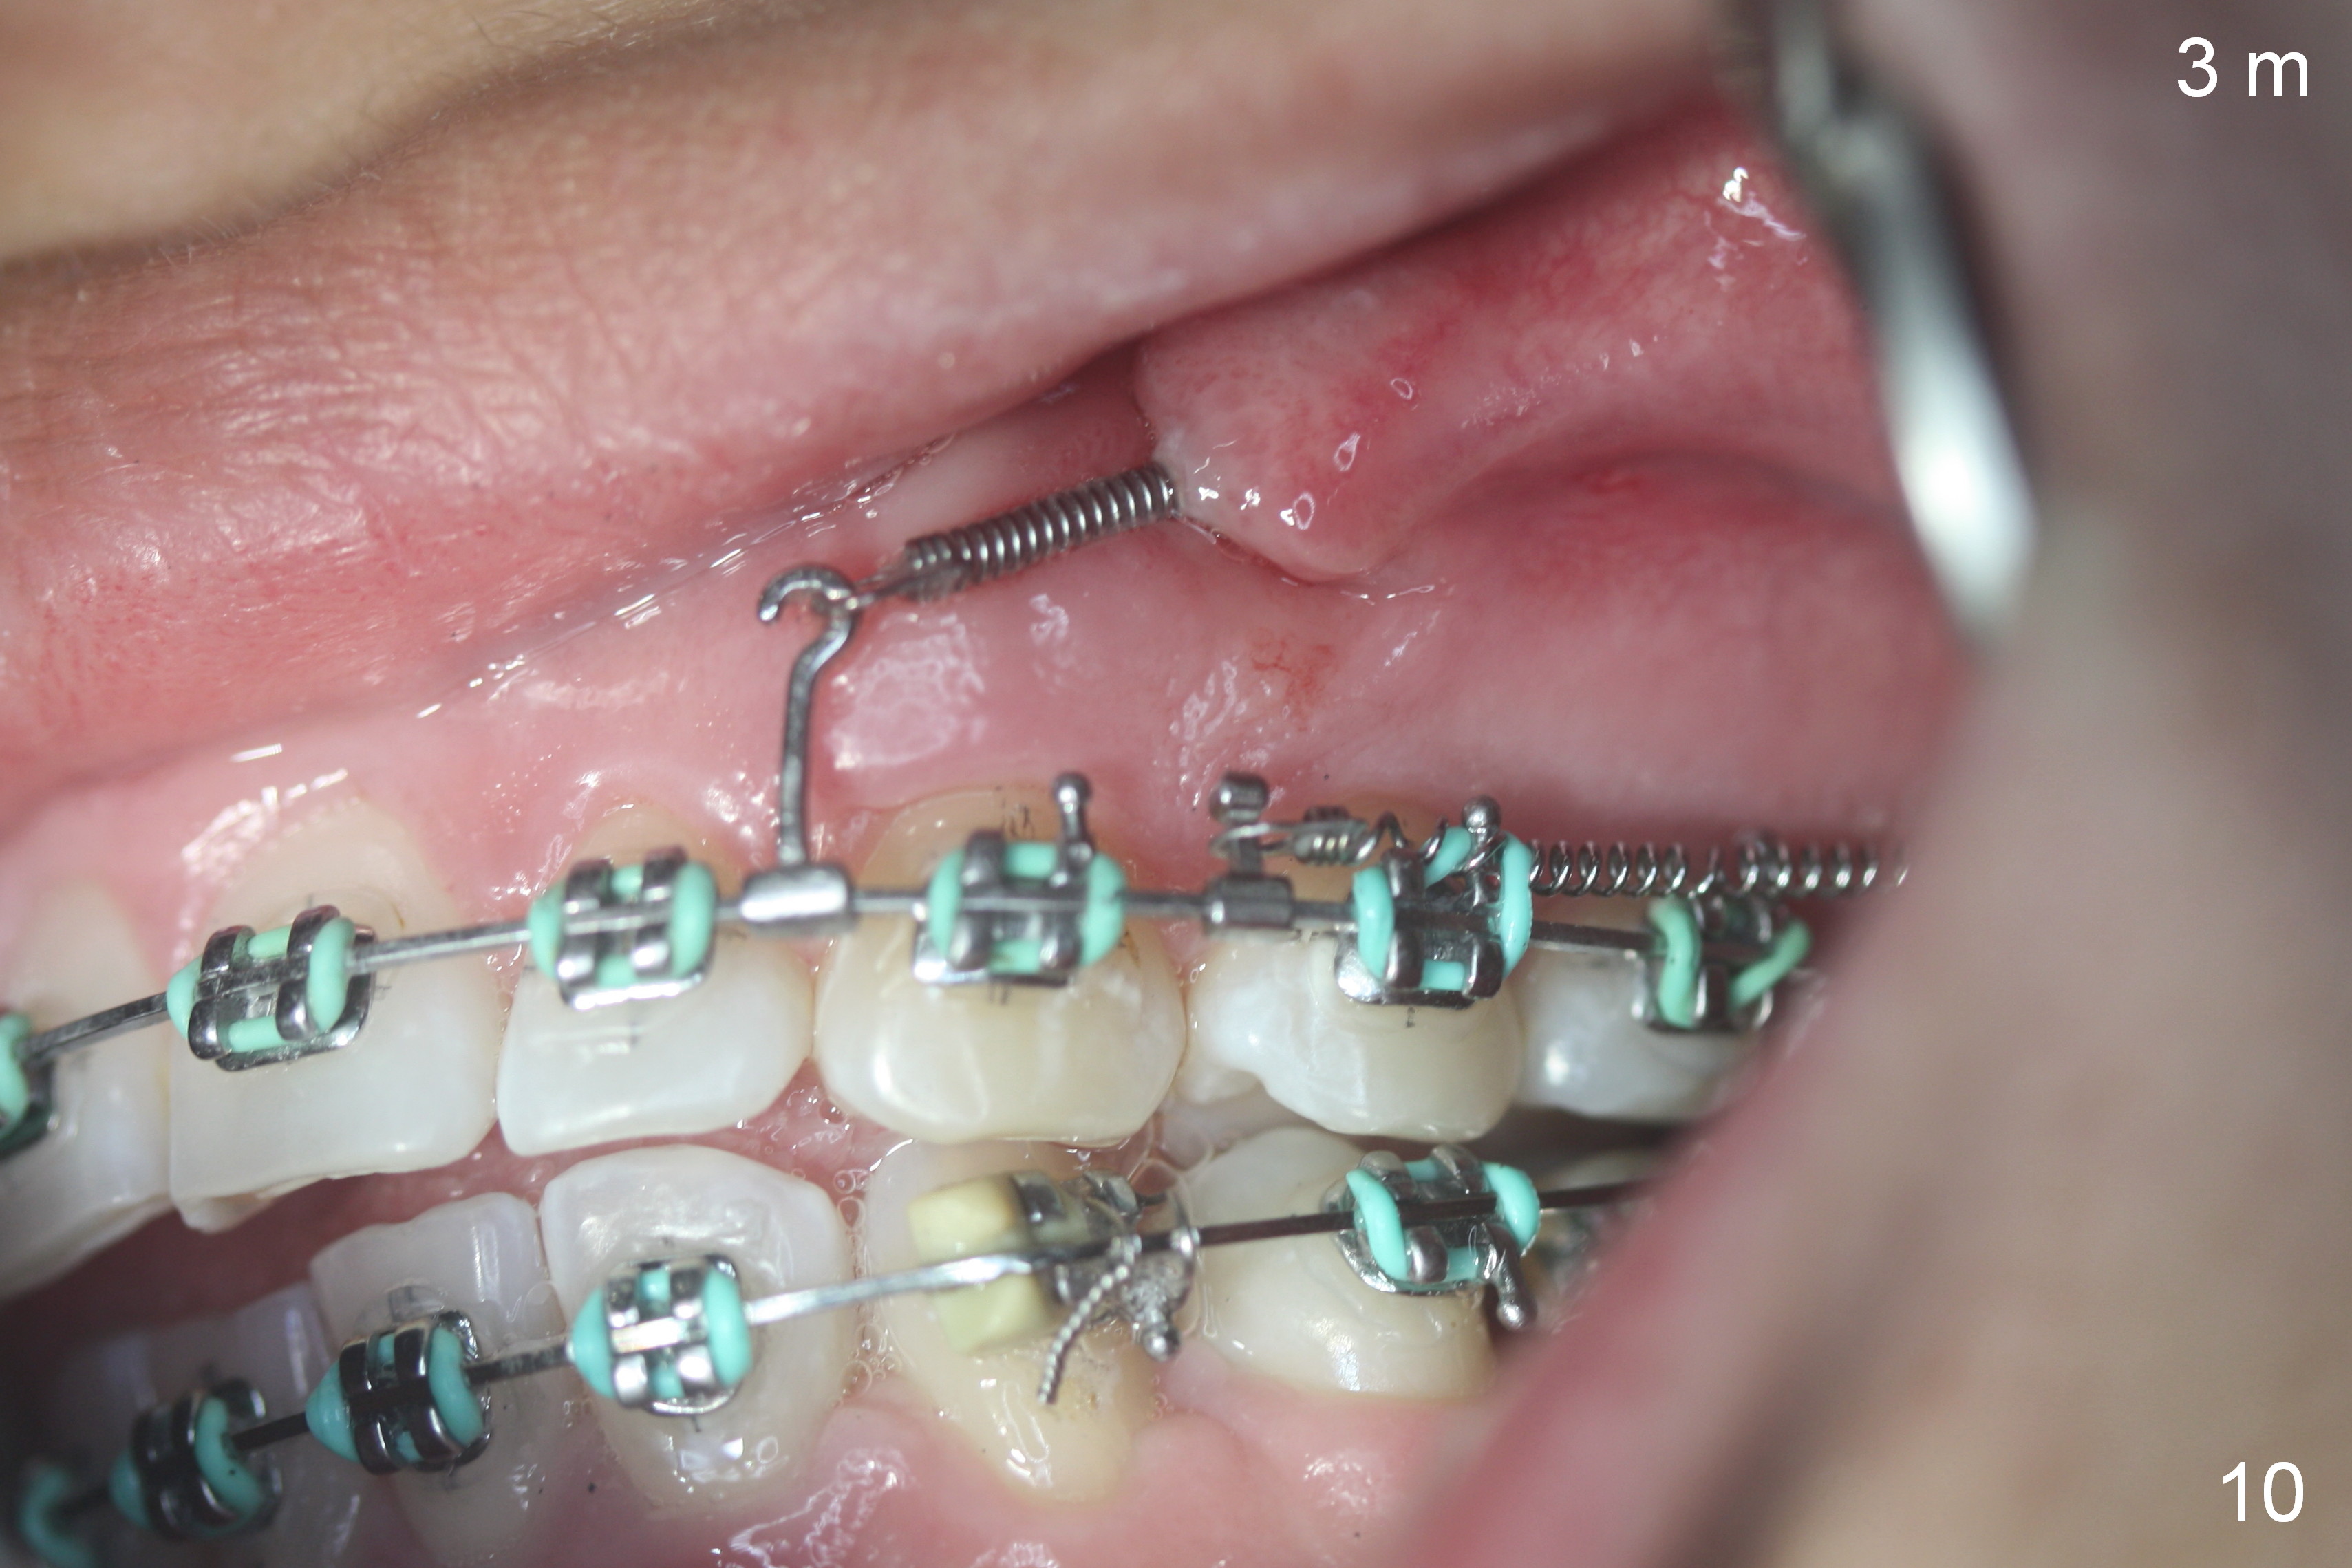

Postop follow up at 1 week (Fig.5,6), 2 months (Fig.7,8) and 3 months (Fig.9,10).  Granulation tissue forms around the entrance of closed coil spring with tenderness 2 months postop (Fig.7,8).  Pain persists especially on the left.  Tension of coiled spring associated with zygomatic implants is low; new coiled springs are added for the posterior implants (Fig.9,10).  Later the left spring associated with the left zygomatic implant fractures.